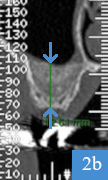

coupe panoramique de dentascanner, 4 mois après la greffe osseusecoupe coronale de dentascanner, hauteur osseuse de 12 mm

Dentascanner 4 mois après la greffe

2a : greffon osseux visible, positionné à l'endroit où il manquait de la hauteur d'os

2b : os sous le sinus mesuré à 12 mm de hauteur ; pose d'un implant possible